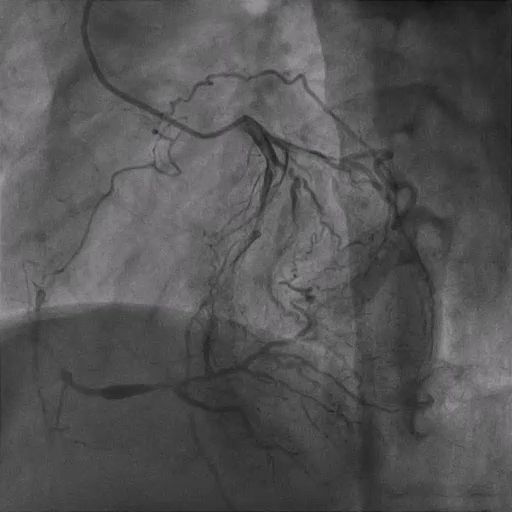

A 71-year-old male smoker with a history of ACS underwent PCI to the LAD and LCX nearly 20 years ago. He presented with recurrent chest discomfort. CTCA revealed an occluded proximal RCA, in-stent restenosis (ISR) in the LAD, and a patent LCX stent. Coronary angiography confirmed LAD Type 4 ISR and ostial RCA CTO with collateral supply. PCI to the LAD ISR was successfully performed, and staged PCI to the RCA CTO was planned. Physical examination was unremarkable.

The RCA CTO had an ambiguous proximal course with a non-tapered stump and an estimated occlusion length of ≈50 mm. Distal vessel quality was good, with collateral filling mainly from the LCX, providing critical information for procedural planning and strategy selection.